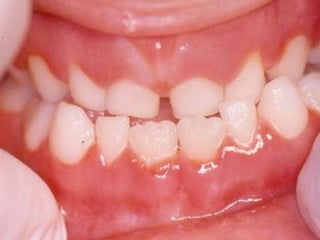

25 - L.C.S., sexo masculino, 18 anos de idade, se apresentou com queixa de aumento de volume na gengiva entre os dentes 23 e 24. Pelo exame clínico, constatamos a presença de um nódulo séssil, de contornos irregulares, coloração avermelhada, com sangramento abundante ao mínimo toque e evolução de 1 ano. O paciente apresentava higiene bucal precária com presença de placa bacteriana e tártaro. Com base no quadro clínico, o diagnóstico é: a) Fibroma e granuloma piogênico. b) Granuloma piogênico e hiperplasia fibrosa inflamatória. c) Lesão periférica (granuloma) de células gigantes e fibroma. d) Granuloma piogênico e lesão periférica (granuloma) de células gigantes. e) Hiperplasia fibrosa inflamatória e fibroma.

Granuloma Piogênico Lesõesnodulares de coloração avermelhada ou vinhosa Provavelmente uma reação inflamatória exagerada ao trauma menor Crescimento rápido, às vezes sangramento espontâneo Ocorre em qualquer idade mas parece mais freqüente em adultos jovens e adolescentes Localização mais comum: gengiva (NEVILLE,2001)

Granuloma Piogênico Lesõesmais antigas, são menos vasculares e mais fibrosas Papila interdental e regiões anteriores são áreas preferenciais, principalmente por vestibular (BORK,1996)